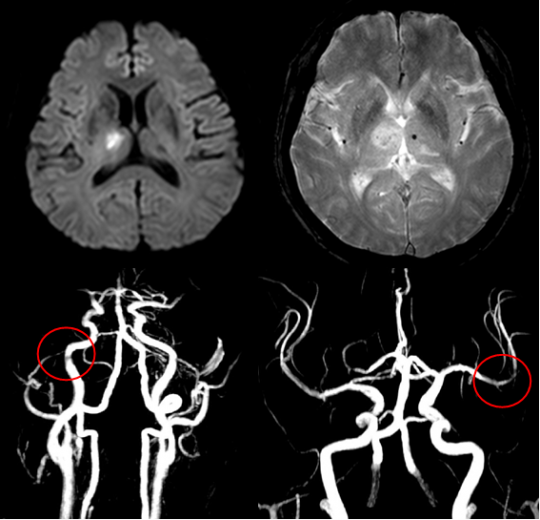

먼저 뇌경색이 무엇인지에 대해 쉽게 설명드리겠습니다. 뇌경색은 뇌로 가는 혈류가 차단되어 발생하는 질병으로, 일반적으로 뇌졸중이라고도 알려져 있습니다. 뇌혈관이 좁아지거나 막히면서 뇌가 필요한 산소와 영양분을 공급받지 못하게 되고, 이로 인해 뇌세포가 손상됩니다. 이러한 손상은 즉각적인 신체 기능 저하를 초래할 수 있으며, 심각한 경우 생명에 지장을 줄 수 있습니다.